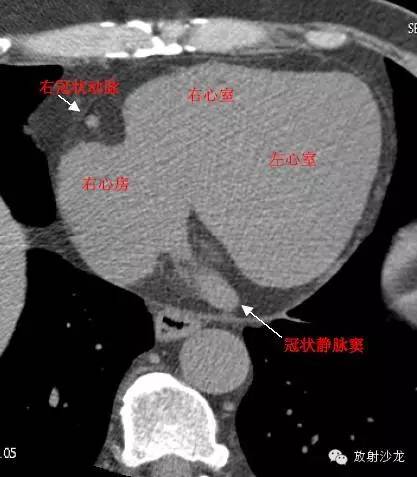

RA -Right Atrium右心房

LV -Left Ventricle左心室

RV -Right Ventricle右心室

RCA -Right Coronary Artery 右冠状动脉

RAA –Right AtrialAppendage右心耳

CS -Coronary Sinus冠状窦